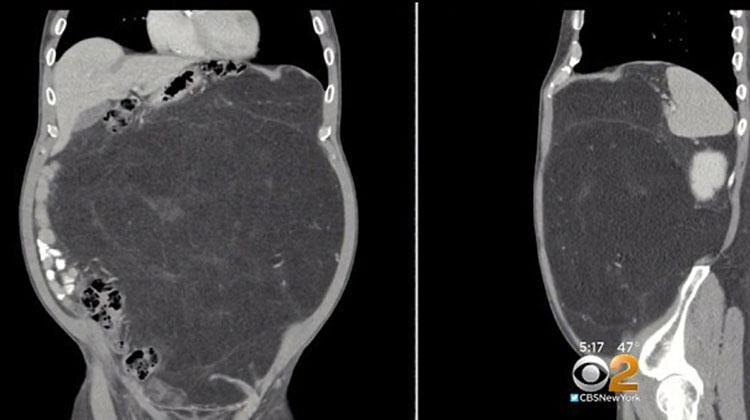

Кевин напугался, что с ним что-то не то и в декабре 2017 года убедил своего лечащего врача отправить его на томографию. Томография показала наличие в животе Кевина крупной опухоли, размером больше футбольного мяча. Кевину был поставлен диагноз липосаркомы. Это раковая опухоль, которая развивается и растет в жировых клетках мягких тканей.

Томография показала, что опасения Кевина насчет инструментов были напрасными, однако там обнаружили куда более страшную вещь - огромная опухоль росла вокруг одной из его почек. Она была самой крупной из всех, что видели врачи этой больницы. "Одно дело видеть это на снимке, но уже совсем другое держать ее в своих руках", - прокомментировал итоги операции хирург Хулио Тейшейра.

По словам врачей чтобы вырасти такой большой (опухоль весила свыше 12 кг), опухоли надо было расти не менее 10-15 лет. Но теперь у Кевина все позади. Он пошел на поправку и его живот теперь в нормальной форме, а все смещенные опухолью внутренности вернулись на свои места.